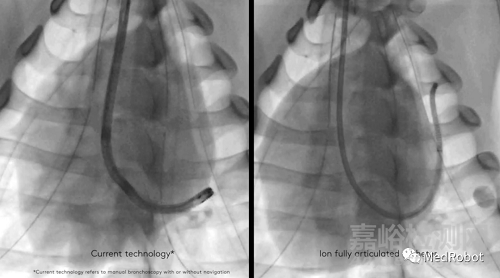

Ion系統(tǒng)包括一個(gè)超細(xì)的人控機(jī)器人導(dǎo)管,可以讓醫(yī)生進(jìn)入難以到達(dá)的呼吸道。形狀感應(yīng)技術(shù),每秒數(shù)百次測(cè)量導(dǎo)管的整個(gè)形狀,以便Ion系統(tǒng)的操作員在整個(gè)導(dǎo)航和活檢過(guò)程中獲得精確的位置和形狀信息。Flexision柔性針與導(dǎo)管一起能夠穿過(guò)曲折的氣道,以便進(jìn)行活組織檢查。

形象一點(diǎn)來(lái)說(shuō),就像現(xiàn)實(shí)生活中用地圖導(dǎo)航。醫(yī)生如果在CT等影像中發(fā)現(xiàn)了藏于肺部偏僻角落的病灶,就需要帶著工具精準(zhǔn)的到達(dá)那個(gè)地方——實(shí)施肺部活檢的過(guò)程就像我們駕車在驚險(xiǎn)而未知的路途中到達(dá)目的地,而Ion是搭載著GPS導(dǎo)航系統(tǒng)又可以靈活移動(dòng)的交通工具。Ion配備的外徑為3.5mm的導(dǎo)管,至少可達(dá)到細(xì)支氣管(G11-G13)。同時(shí)導(dǎo)管頭部還可以進(jìn)行180度的偏轉(zhuǎn),輔助醫(yī)生在小而彎曲的氣管中,導(dǎo)航導(dǎo)管到達(dá)病灶,通過(guò)專用的活檢針穿過(guò)導(dǎo)管收集周圍的肺部組織。

Ion的超細(xì)機(jī)械導(dǎo)管和先進(jìn)的可操作性使導(dǎo)航遠(yuǎn)至周圍的肺部,其2.0毫米工作通道和3.5毫米外徑導(dǎo)管可以穿過(guò)難以導(dǎo)航的小氣道到達(dá)肺的所有18個(gè)部位。Ion系統(tǒng)的外圍視覺(jué)探針可在導(dǎo)航期間提供直接視覺(jué),光纖傳感技術(shù)讓醫(yī)生可以隨時(shí)準(zhǔn)確了解導(dǎo)管的精確位置和形狀信息且不易受到干擾。